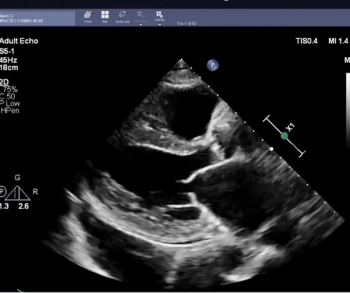

In order to facilitate optimal detection and assessment of liver fibrosis and steatosis, the newly launched Hepatus 6 Diagnostic Ultrasound System offers the capabilities of real-time two-dimensional ultrasound with visual transient elastography in one device.